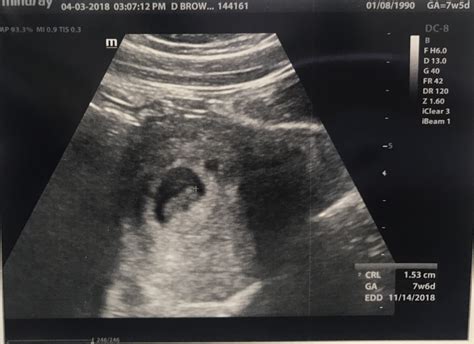

When you arrive for your appointment, the procedure is typically straightforward. Depending on the clinical protocol of your healthcare provider, you might undergo either a transabdominal ultrasound (where the probe is moved over your belly) or a transvaginal ultrasound (where a slim probe is inserted into the vagina). Because the baby is still very small at nine weeks, a transvaginal scan often provides a much clearer, high-resolution image.

By the time you reach an ultrasound at 9 weeks, your baby has officially transitioned from the embryonic stage to the fetal stage. While they are only about the size of a green olive or a grape—roughly 0.9 inches long—their growth is nothing short of miraculous. During the scan, your sonographer may point out several specific physical features that have begun to emerge.

The primary purpose of an early scan is clinical accuracy. Your healthcare provider uses the ultrasound at 9 weeks to gather essential data that will guide the rest of your prenatal care. Below is a breakdown of what the clinical team typically monitors during this visit:

Diagnostic Goal Purpose

Crown-Rump Length (CRL) The measurement from the top of the head to the bottom of the torso, used to confirm the gestational age and due date.

Heart Rate Monitoring Confirms the viability of the pregnancy and checks for a strong, rhythmic heartbeat.

Number of Fetuses Confirms whether you are carrying a singleton, twins, or more.

Placental Placement Checks the initial location of the gestational sac and developing placenta.

It is important to remember that at nine weeks, your baby is still very small. The image on the screen will not look like the "classic" newborn baby you might be imagining; it will likely resemble a small, active blob. Do not be discouraged if you cannot distinguish individual features immediately; the sonographer is trained to interpret these early images and will guide you through what you are seeing.

The ultrasound at 9 weeks is often considered the most accurate way to date a pregnancy. While many people calculate their due date based on the first day of their last menstrual period, this method assumes a perfect 28-day cycle. If your cycles are irregular, your ovulation might have occurred later or earlier than expected. The ultrasound measurement, known as the CRL, provides a scientifically accurate date that will be used for all subsequent prenatal care, including future screening tests and induction planning.